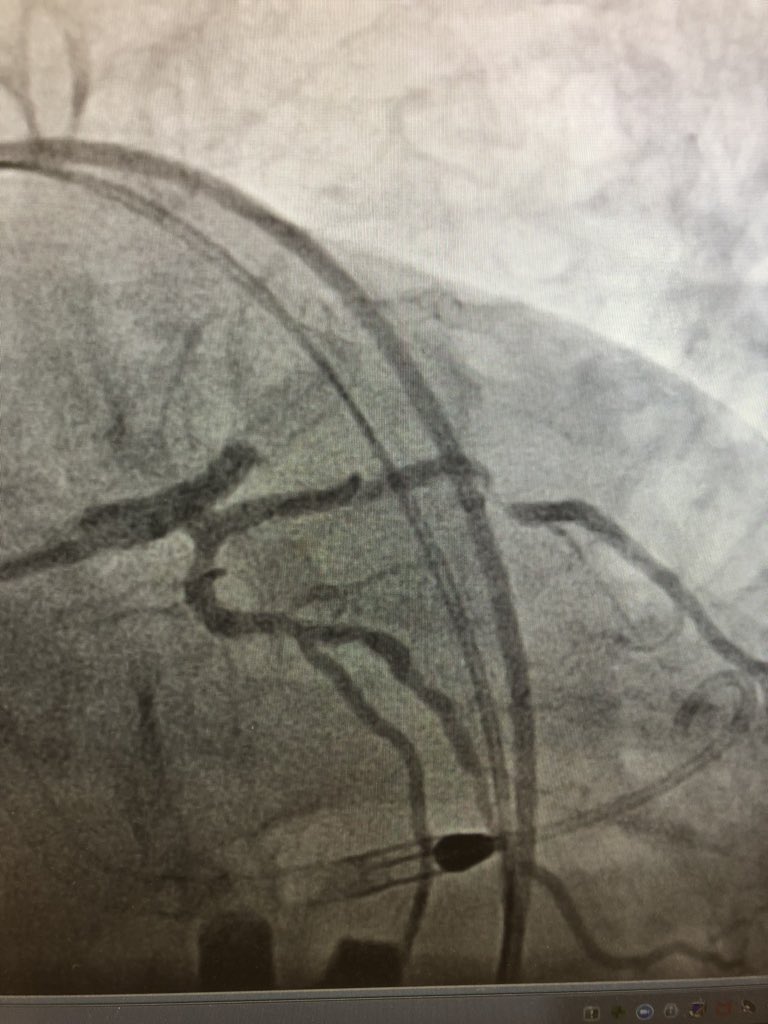

Always Angio w 4F #Micropuncture sheath before #Ax #Largeboreaccess @AntoniousAttall @payalkohlimd @sjgips @aelsab @Michel_CorbanMD @EmileMehanna @essadii @SamKMehta @fjsawaya @evhaddad @dimitri_zappi @gbiondizoccai @sbrugaletta @twj1974 @mmamas1973 @nickaram @crfheart @TCTMD